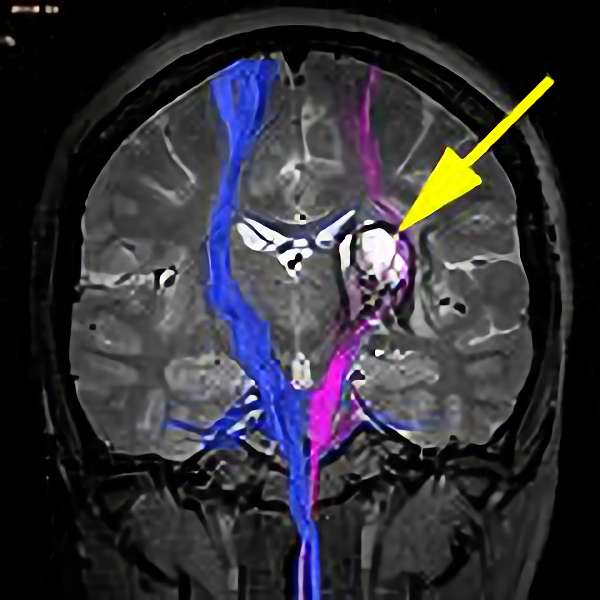

'22年1月

30代

富永/

松田,北島,殿元

中脳

出血性海綿状血管腫

再出血の予防目的

山口県の病院より紹介

Rt-supracerebellar

infratentorial

approach

No.No.48 手術前1

No.No.48 手術前2

No.No.48 手術後1

No.No.48 手術後2

CT/MRにより完全に摘出されたことが確認された